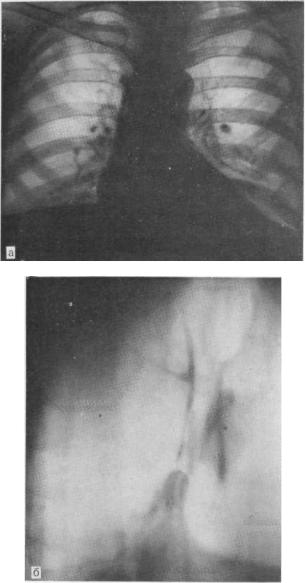

Рентгеновские снимки тератомы средостения: Диагностика и лечение

Раздел: Фотоэссе